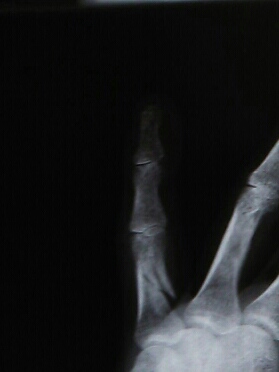

金曜にレントゲン撮ったけどあんまり変わってない…。

何故だか添え木は外され指を動かすリハビリモードに切り替わった!?

まだくっついてないし痛いんですけど…。

どういうこと?って聞いても説明ないし、訳わからんから